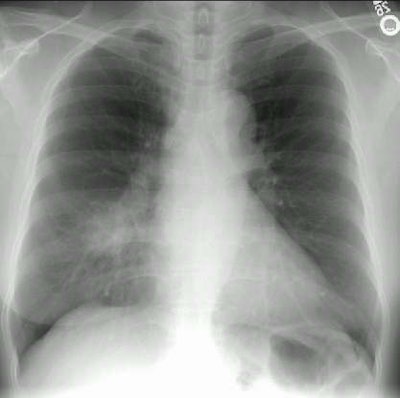

Rounded Pneumonia

Although most commonly found in children, adults can present with rounded pneumonia. This middle-aged female patient presented with a cough and fever. Her chest radiograph revealed a rounded density which was located in the right middle lobe. Because the patient had a smoking history there was a concern that she might have a lung cancer. Clinically, however, the patient appeared to have a pneumonia and she was treated with antibiotics.

Follow-up CXR demonstrated resolution of the rounded pneumonia after completion of antibiotic therapy.